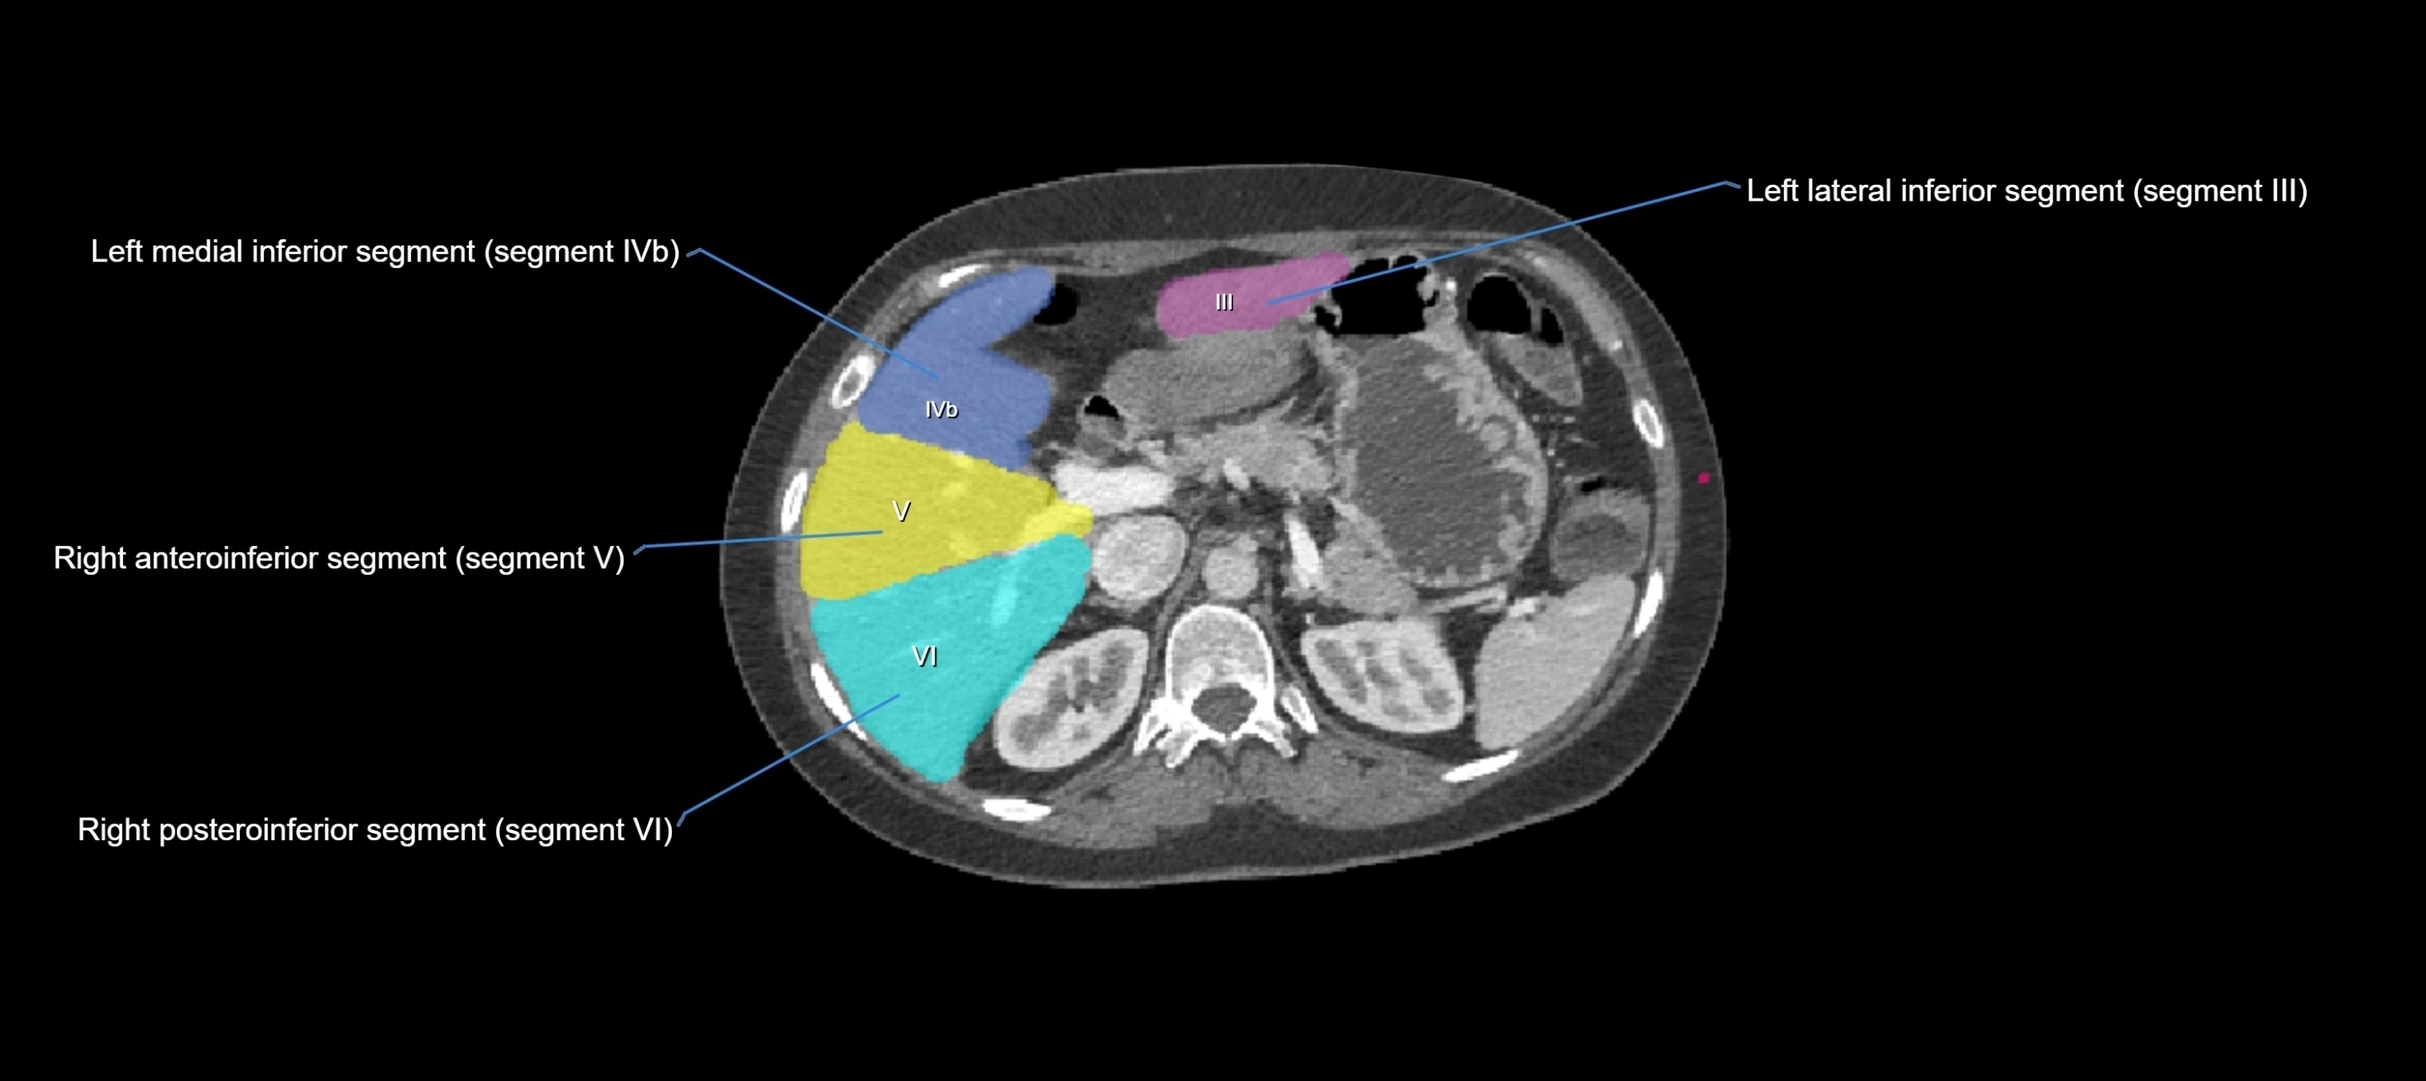

CT Image

image